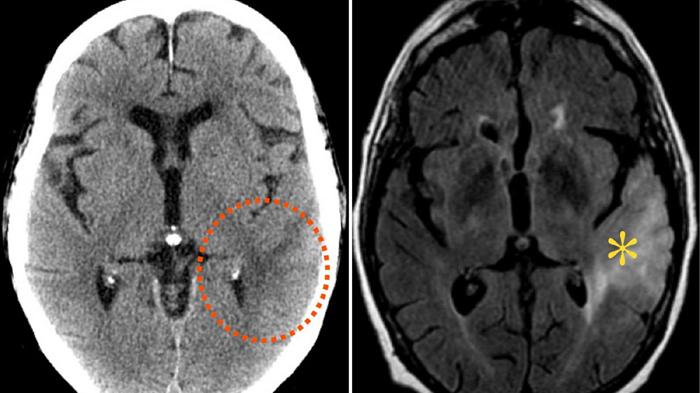

TRIBUN-BALI.COM - Tumor otak pada anak bukan hal baru, tapi sudah jadi kasus yang cukup sering.

Begini tanda-tanda yang bisa Anda amati pada anak yang menderita tumor otak sebelum terlambat.